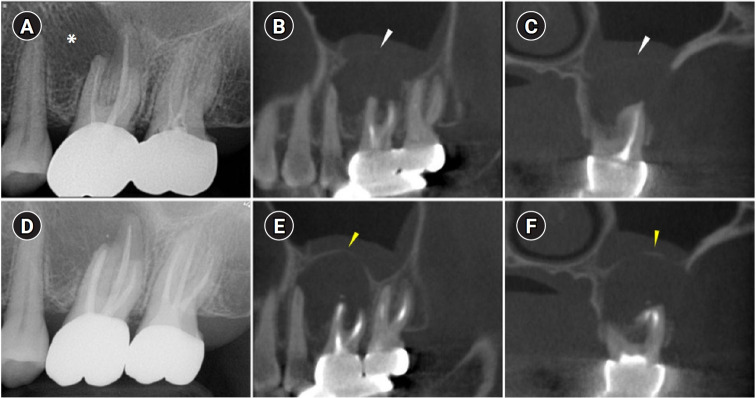

When root canal infections breach the maxillary sinus floor (MSF), maxillary sinusitis of endodontic origin (MSEO) can result. This case illustrates the surgical management of MSEO following the nonsurgical reestablishment of the MSF. A 55-year-old woman presented with left facial pain and was diagnosed with MSEO originating from the left upper first molar. Despite undergoing nonsurgical root canal treatment, there was no evidence of bony healing after 6 months. However, cone-beam computed tomographic (CBCT) scans revealed the reestablishment of MSF. Subsequently, surgical intervention was carried out using a dental operating microscope. Two years after surgery, CBCT images indicated that the mucosal edema had resolved, and the MSF was well reestablished. Preserving the MSF is crucial for the success of endodontic surgery. When MSEO is present, the integrity of the MSF must be assessed to determine appropriate treatment options.